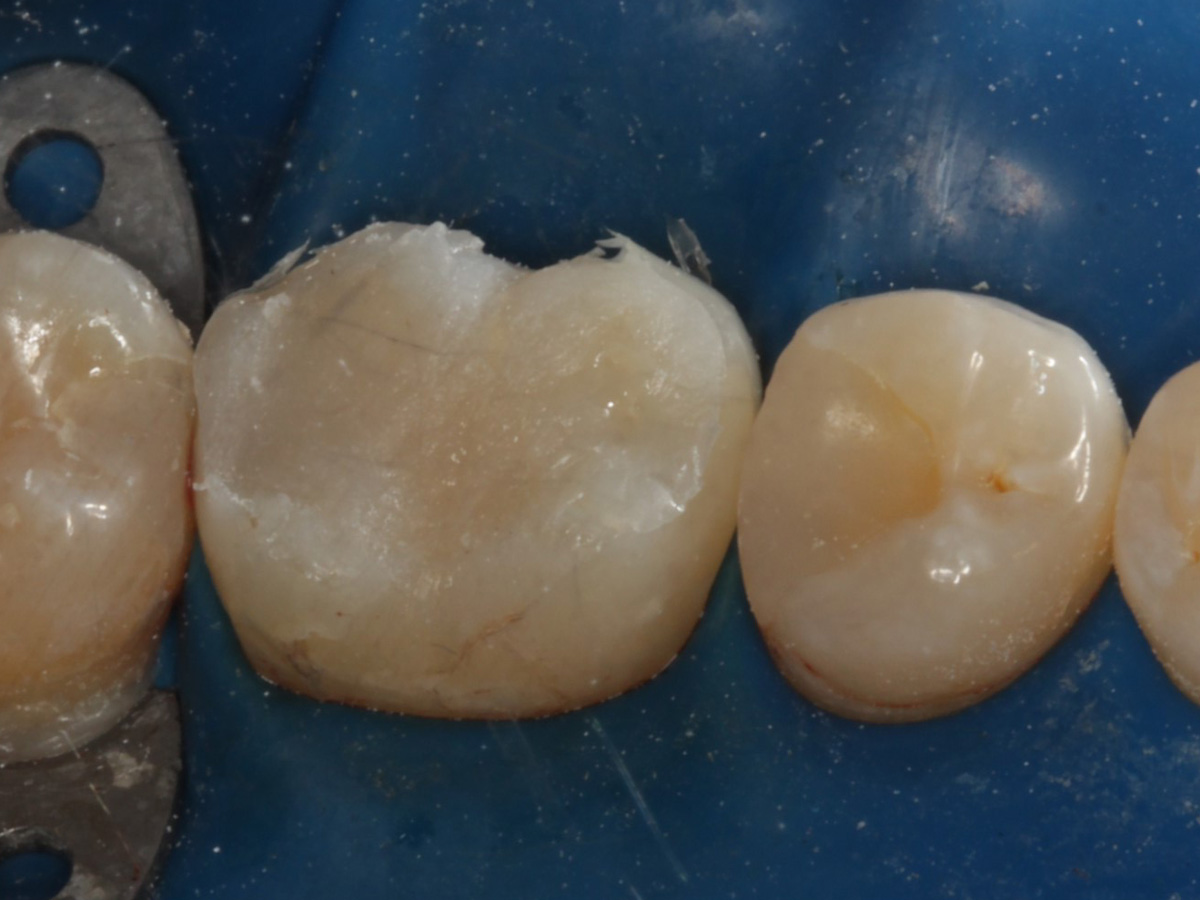

Kavitäten gefüllt (Injektion Moulding: Flowkomposit, erwärmtes Seitenzahnkomposit aus Karpule)

Abbildung 20

Abbildung 21

Zahnseidenkontrolle: kein Überschuss, satte Kontaktpunkte

Abbildung 22

Fertige Restauration Zahn 46